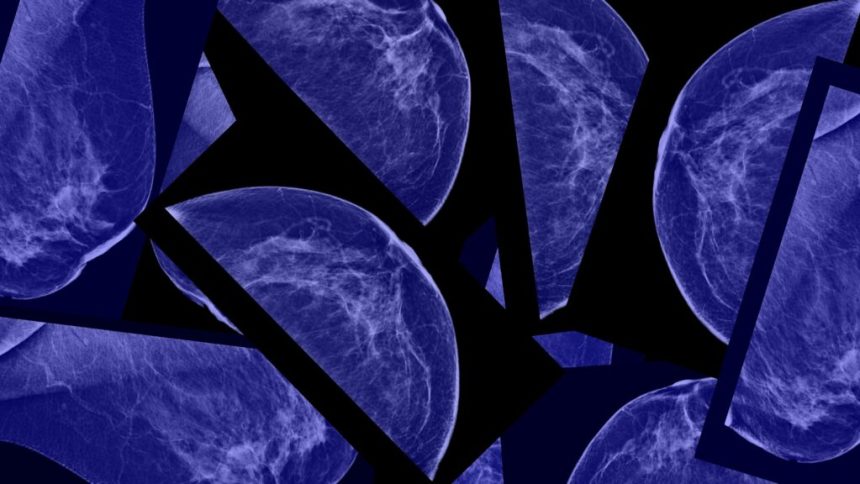

AI is also making waves in the field of mammograms, where predictive algorithms are being developed to assess the risk of breast cancer and cardiovascular disease. The FDA recently authorized an algorithm that uses breast imaging to predict a patient’s risk of developing breast cancer in the next five years, showcasing the potential of AI in preventive healthcare.